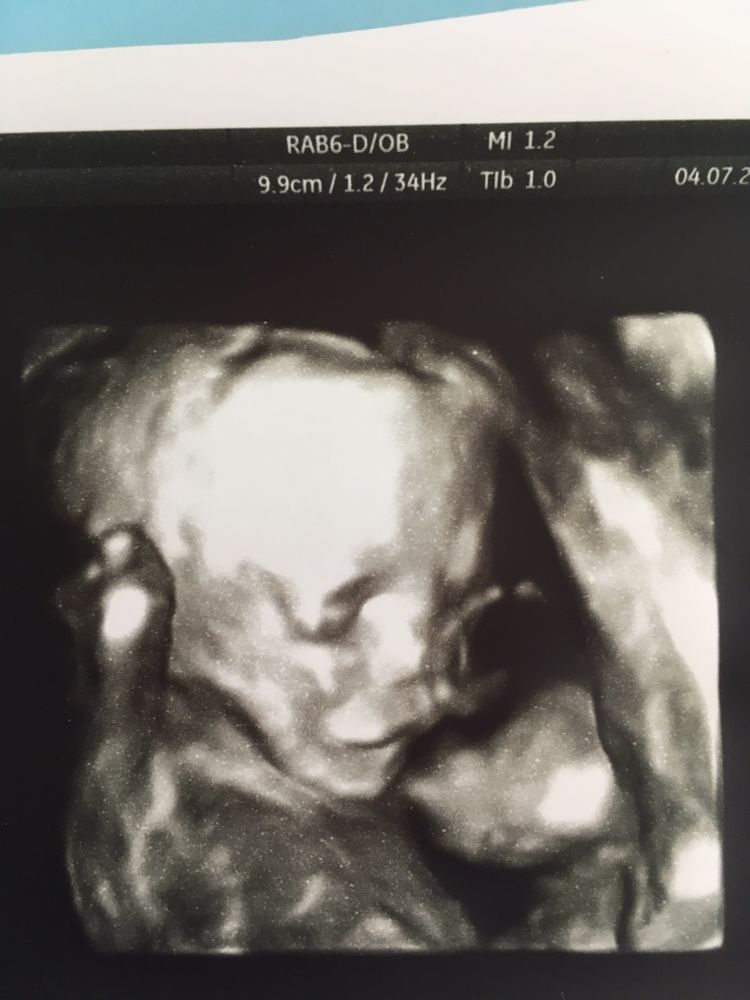

Многоплодная беременностьДевочки, стоит ли делать 3д узи на 17 неделе? Многоплодная беременность, может делал кто то, видно там что то или это просто транжирство? Хотела бы примеры глянуть, а то и так трудно материально, стоил ли или нет

Одно фото на 17 неделе, а второе на втором скрининге